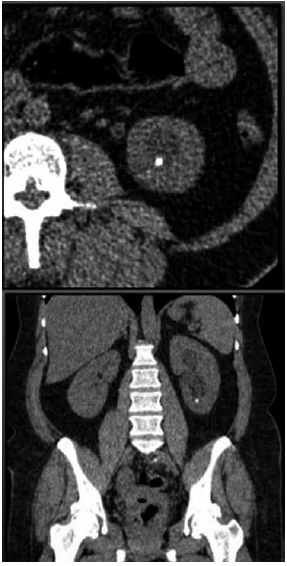

Mulher de 48 anos apresenta quadro de dor recorrente em região lombar à esquerda. Realizado tomografia de abdome total sem contraste (imagem demonstrada), que evidenciou cálculo em cálice inferior de 0,7 cm (400 UH). A análise da via de saída do cálice inferior demonstrou: ângulo infundíbulo-pielico de 95 graus e infundíbulo com comprimento de 1,0 cm.

Qual a melhor proposta para a paciente?